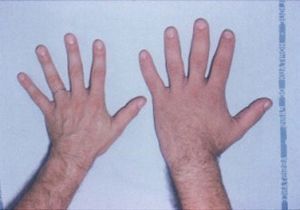

تضخم الأطراف Acromegaly هى حالة ينَتجُ عنها تمدد في عظام الوجه والقدمين واليدين. ومعظم حالات تضخم الأَطراف يُسبِّبها تورم الغدَّة النُّخاميَّة، وتحدث عند الأَشخاص ذوي الطول الطبيعي.